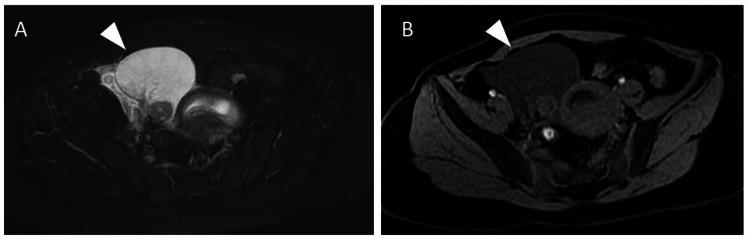

Massive ovarian edema (MOE) is a rare benign condition presenting as unilateral ovarian enlargement with stromal edema, and only a limited number of MOE cases during pregnancy have been reported. MOE is often complicated by ovarian torsion, which requires detorsion. Although the diagnosis of MOE can be made using ultrasound and magnetic resonance imaging, its rarity makes diagnosis difficult, usually leading to overtreatment. Preserving the ovary in the treatment of MOE torsion is essential, and consideration of oophoropexy after detorsion is often reported. However, fixing an enlarged ovary to the pelvic wall in the limited space of the pelvis is challenging. Herein, we present a case of MOE of the right ovary diagnosed at the fifth week of gestation after ovulation induced by clomiphene citrate. Torsion of the ovary occurred in the seventh week. We achieved preservation of the ovary through laparoscopic surgery with detorsion and drainage by making a small incision to the enlarged ovary, resulting in an immediate size reduction. There was no recurrence of torsion or MOE throughout the pregnancy, and the patient gave birth in the 39th week of gestation. This is the third reported case of MOE after ovulation using clomiphene citrate, and it highlights the effectiveness of treatment with detorsion and a small incision of the ovary via laparoscopic surgery in patients with MOE torsion during pregnancy.

摘要

巨大卵巢水肿(MOE)是一种罕见的良性疾病,表现为单侧卵巢肿大伴间质水肿,妊娠期间仅有少数MOE病例的报道。MOE常并发卵巢扭转,需要进行扭转复位。虽然MOE的诊断可通过超声和磁共振成像做出,但其罕见性使得诊断困难,通常导致过度治疗。在MOE扭转的治疗中保留卵巢至关重要,扭转复位后常考虑卵巢固定术。然而,在骨盆有限的空间内将肿大的卵巢固定于骨盆壁具有挑战性。在此,我们报告一例在枸橼酸氯米芬诱导排卵后妊娠第5周诊断为右侧卵巢MOE的病例。卵巢在第7周发生扭转。我们通过腹腔镜手术进行扭转复位和引流,在肿大的卵巢上做一个小切口,使卵巢立即缩小,从而成功保留了卵巢。整个孕期未再发生扭转或MOE,患者在妊娠第39周分娩。这是第三例报道的枸橼酸氯米芬促排卵后发生MOE的病例,它突出了腹腔镜手术对妊娠期间MOE扭转患者进行扭转复位和卵巢小切口治疗的有效性。